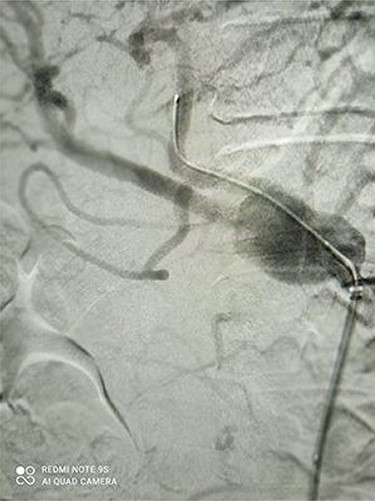

CT angiography revealed a saccular aneurysm in the right trunk of the celiac artery (42*56*59 mm) with thrombus formation lining its wall. The aneurysm lumen was patent and had a diameter of 20*21*34 mm. With a 12-mm patent neck, the aneurysm was connected to the main artery. The aneurysm was surrounded by distal branches of the left gastric, common hepatic and splenic arteries. A percutaneous angiographic intervention was suggested to the patient, and he was asked to go to NPO from midnight. After prepping and draping, a right femoral artery puncture was performed under local anesthesia, and a 6 French angiographic sheath (Arrow®) was inserted. The 6 French JR catheter (Alvision™) was extended to the aorta via a hydrophilic wire (AqWire®) and contrast media was injected, revealing a celiac artery aneurysm. The 8F*40 (Arrow®) sheath was then replaced, and the celiac artery was cannulated, and two 40*10 and 40*9 mm covered stents (Fluency™) were inserted through a stiff park wire (Amplatz Emerald). Finally, good results were obtained, with full aneurysmal coverage and distal celiac artery patency. Three days after the patient was admitted to the ward, a CT angiography revealed good results with complete coverage of the aneurysmal area and no leakage.

Figures 3 and 4 show CT angiography findings after the endovascular intervention.